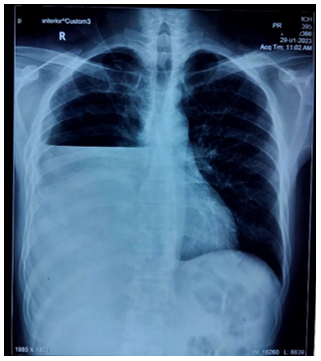

A 40-year-old male, who was a chronic smoker and alcoholic for 20 years and a cocaine abuser 5 years who presented to the medicine emergency of Government Medical college and Hospital Chandigarh, with complaints of shortness of breath for 1.5 months which exacerbated over the last 4 days and right pleuritic sided chest pain x 4 days and fever (high grade, 102F) and cough with mild expectoration x 4 days. It was not associated with wheeze, or haemoptysis, swelling in the lower extremities, weight loss or anorexia. There was no history of any significant comorbidities. He had no history of tuberculosis or contact history of tuberculosis, or any known comorbidities. General physical examination was unremarkable. Chest X Ray done on admission was suggestive of right sided moderate pleural effusion. Pleural tap done under Ultrasound guidance was done showing a green coloured thick and viscous fluid which was suggestive of full field pus cells in the fluid with gram staining showing gram positive cocci in chains(?streptococci) , and fluid protein 2.1gm%, fluid ADA 147 IU/L, glucose 10. Patient was started on broad spectrum antibiotics after sending 3 sets of blood cultures and pus cultures. An Intercostal tube was inserted in view of empyema and the tube started draining frank green pus. Patient started showing clinical improvement on broad spectrum antibiotics 9injection piperacillin tazobactam) on day 2 and day three of therapy. Antitubercular therapy was not started during stay. Blood cultures sent were sterile after 5 days of incubation as well as pus cultures and sputum cultures showed mixed flora. 2D Echo done to rule out infective endocarditis was suggestive of a normal ejection fraction and no evidence of vegetation, clot, pericardial effusion. On day 5 of admission, ICD was removed after no evidence of pleural effusion and fully expanded lung. ICD was removed subsequently after pulmonology consult and patient was discharged on oral antibiotics.

Figure showing the Chest x ray of the patient at presentation